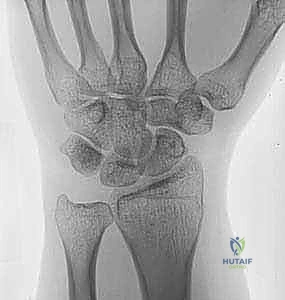

- الفحص السريري الشامل: يبدأ بفحص المرفق، الرسغ، والكتف لاستبعاد أي إصابات متزامنة (مثل متلازمة إيسيكس-لوبريستي Essex-Lopresti). يتم فحص النبض والأعصاب بدقة لضمان عدم وجود إصابة وعائية أو عصبية.

- الأشعة السينية (X-rays): يتم أخذ صور بأوضاع مختلفة (أمامي خلفي، جانبي، ومائل) لرؤية الكسر بوضوح. أحياناً يكون الكسر دقيقاً جداً ولا يظهر إلا من خلال علامة "وسادة الدهون المرفوعة" (Positive Fat Pad Sign) التي تشير إلى وجود نزيف داخل المفصل.